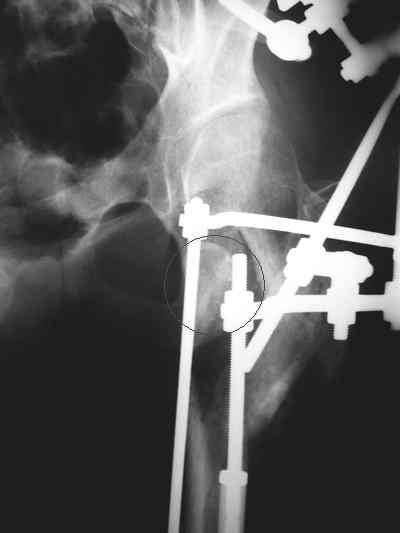

Девушка 21 года 02.10.07 г. пострадала в результате падения с высоты 4-го этажа при пожаре в одном из студенческих общежитий г. Москвы. Получила тяжелую сочетанную травму, в том числе закрытый оскольчатый чрез- и подвертельный перелом левой бедренной кости. Лечилась в одной из больниц столицы. Бедро было фиксировано при помощи скелетного вытяжения. Через полтора месяца после травмы переведена в институт им. Склифосовского. У больной имелись: поддиафрагмальный абсцесс, трахеопищеводный свищ, трахеостома, гастростома, несостоятельность швов раны передней брюшной стенки, укорочение левого бедра на 10 см (рентгенограммы при поступлении - рис 1.). В середине декабря был наложен спицестержневой аппарат, с помощью которого к сегодняшнему удалось устранить укорочение бедра (рис. 2). В течение последних 4-х дней устраняем смещение дистального отломка бедренной кости по ширине. Раны на передней брюшной стенке почти зажили. Температура тела и лабораторные показатели нормальные. Планируем выполнить закрытый остеосинтез левой бедренной кости удлиненным проксимальным бедренным штифтом производства фирмы "Остеомед". Нас смущает, что малый вертел бедренной кости остается значительно смещенным проксимально и кнутри.

Мы закончили репозицию отломков бедренной кости в аппарате (рис. 1, 2) у нашей пациентки и на прошлой неделе сделали ей вторую операцию. Штифт удалось ввести закрыто. Верхний шеечный винт держался очень плохо, поэтому мы его убрали и решили не ставить. Нижний держал очень плотно. Рентгенограммы после операции прилагаю (рис. 3,4). Пока не получилось сделать нормальный аксиальный снимок (больная с трудом сгибает и отводит ногу в тазобедренном суставе). Пока сделали боковую проекцию в положении на здоровом боку со сгибанием здоровой ноги.